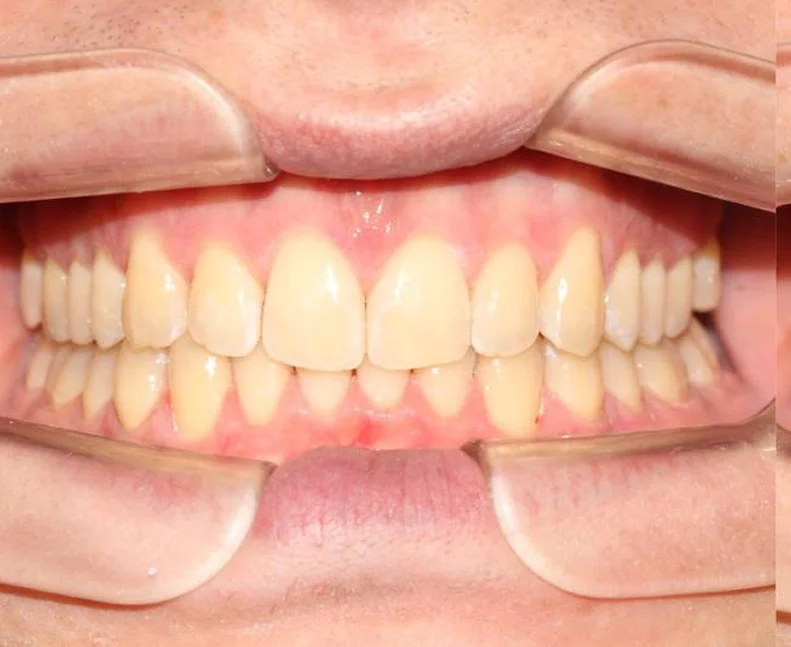

Установка ретейнеров на нижнюю и верхнюю челюсть

Фотографии опубликованы с согласия пациента

Дьячкова Инна Владимировна

Стоматолог - ортодонт

Стаж более 11 лет